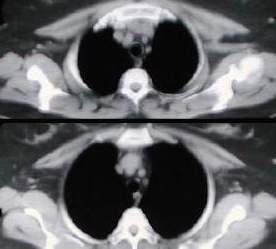

• Estudios de tomografía del tórax, electromiografía, expirometría y prueba terapeutica con edrofonio, son realizados, concluyendo el diagnóstico de miastenia gravis con Timoma, (16 meses despues de iniciados los síntomas).

Tomografía torácica